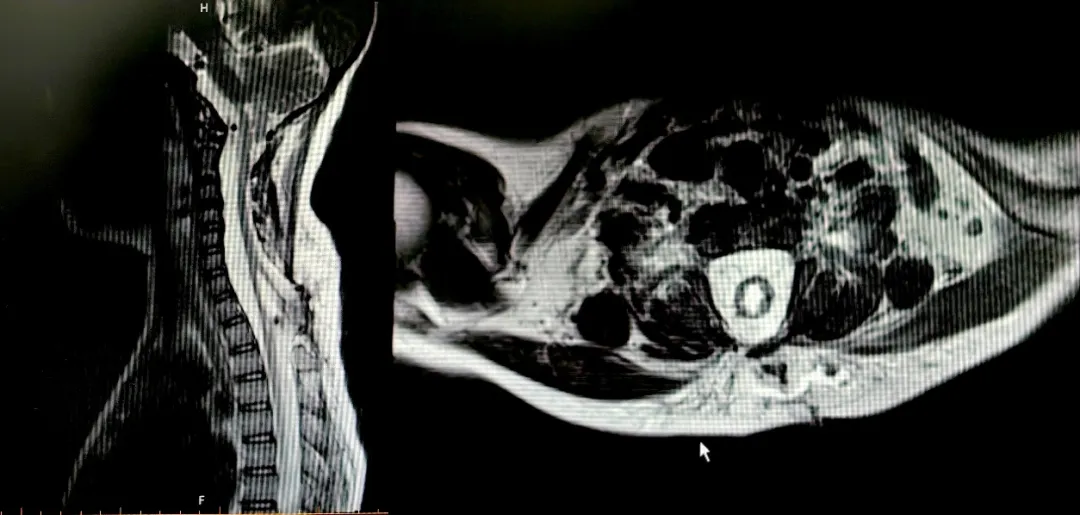

A postoperative review of Yang Yang's cervical spine MRI showed complete reabsorption of the spinal cord, and the surgical results were satisfactory

After admission, Dr. Duan arranged a series of examinations and assessments for Yang Yang. Dr. Xing Tianying from the Department of Urology was invited to perform a detailed urodynamic examination to assess whether there was neurogenic lower urinary tract dysfunction. Technician Zhang Mo from the Department of Radiology completed a detailed imaging scan, which revealed the fine structure of the bulging spinal cord.